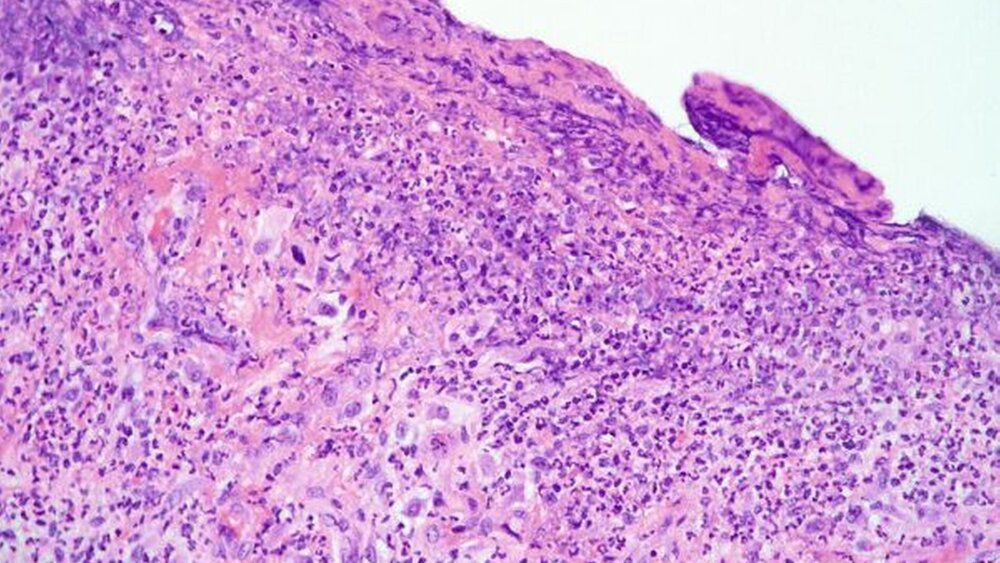

Die histopathologische Untersuchung ergab eine Zyste mit mehrschichtigem, nicht verhornendem Plattenepithel sowie fibrosiertes Bindegewebe mit deutlicher lymphozytärer Infiltration (Abbildungen 5 a und b), passend zum klinischen Bild einer entzündlich überlagerten, radikulären Zyste.